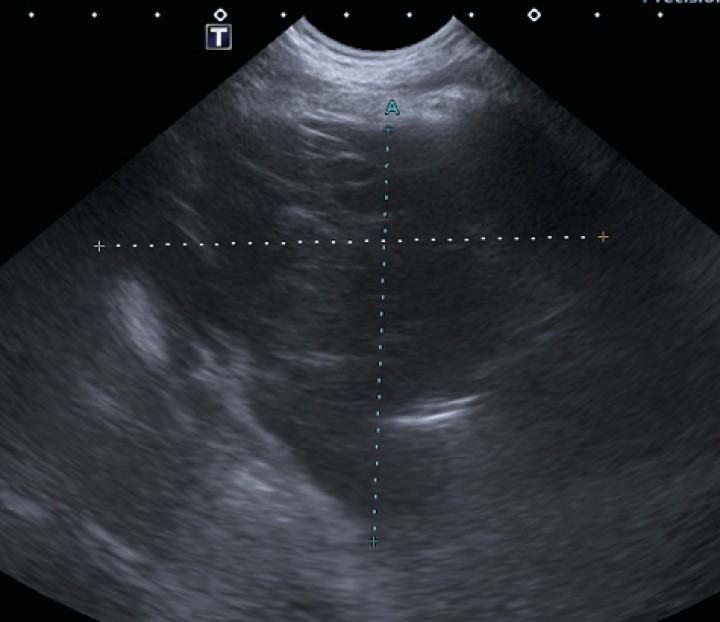

En vista de los hallazgos torácicos, se realizó una ecografía abdominal (Fig. 4) con el fin de descartar otras posibles lesiones. Dicho estudio mostró la presencia de un nódulo hipoecoico (9 x 6 mm), de bordes poco definidos y no vascularizado empleando el Doppler color, en la cola esplénica. Los posibles diferenciales incluyeron un infiltrado metastásico o lesión benigna (hiperplasia nodular, hematopoyesis extramedular). El resto del abdomen fue normal.

<p>Nódulo hipoecoico observado en el parénquima esplénico durante la realización de la ecografía abdominal.</p>

Nódulo hipoecoico observado en el parénquima esplénico durante la realización de la ecografía abdominal.